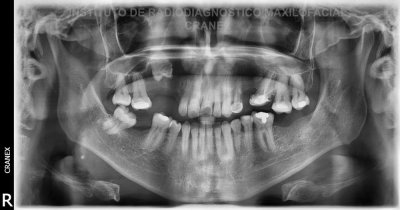

Caso Radiográfico n° 03: Ameloclasia

Paciente de 46 años de edad de sexo masculino, que acude a nuestra institución para evaluación radiográfica de rutina.